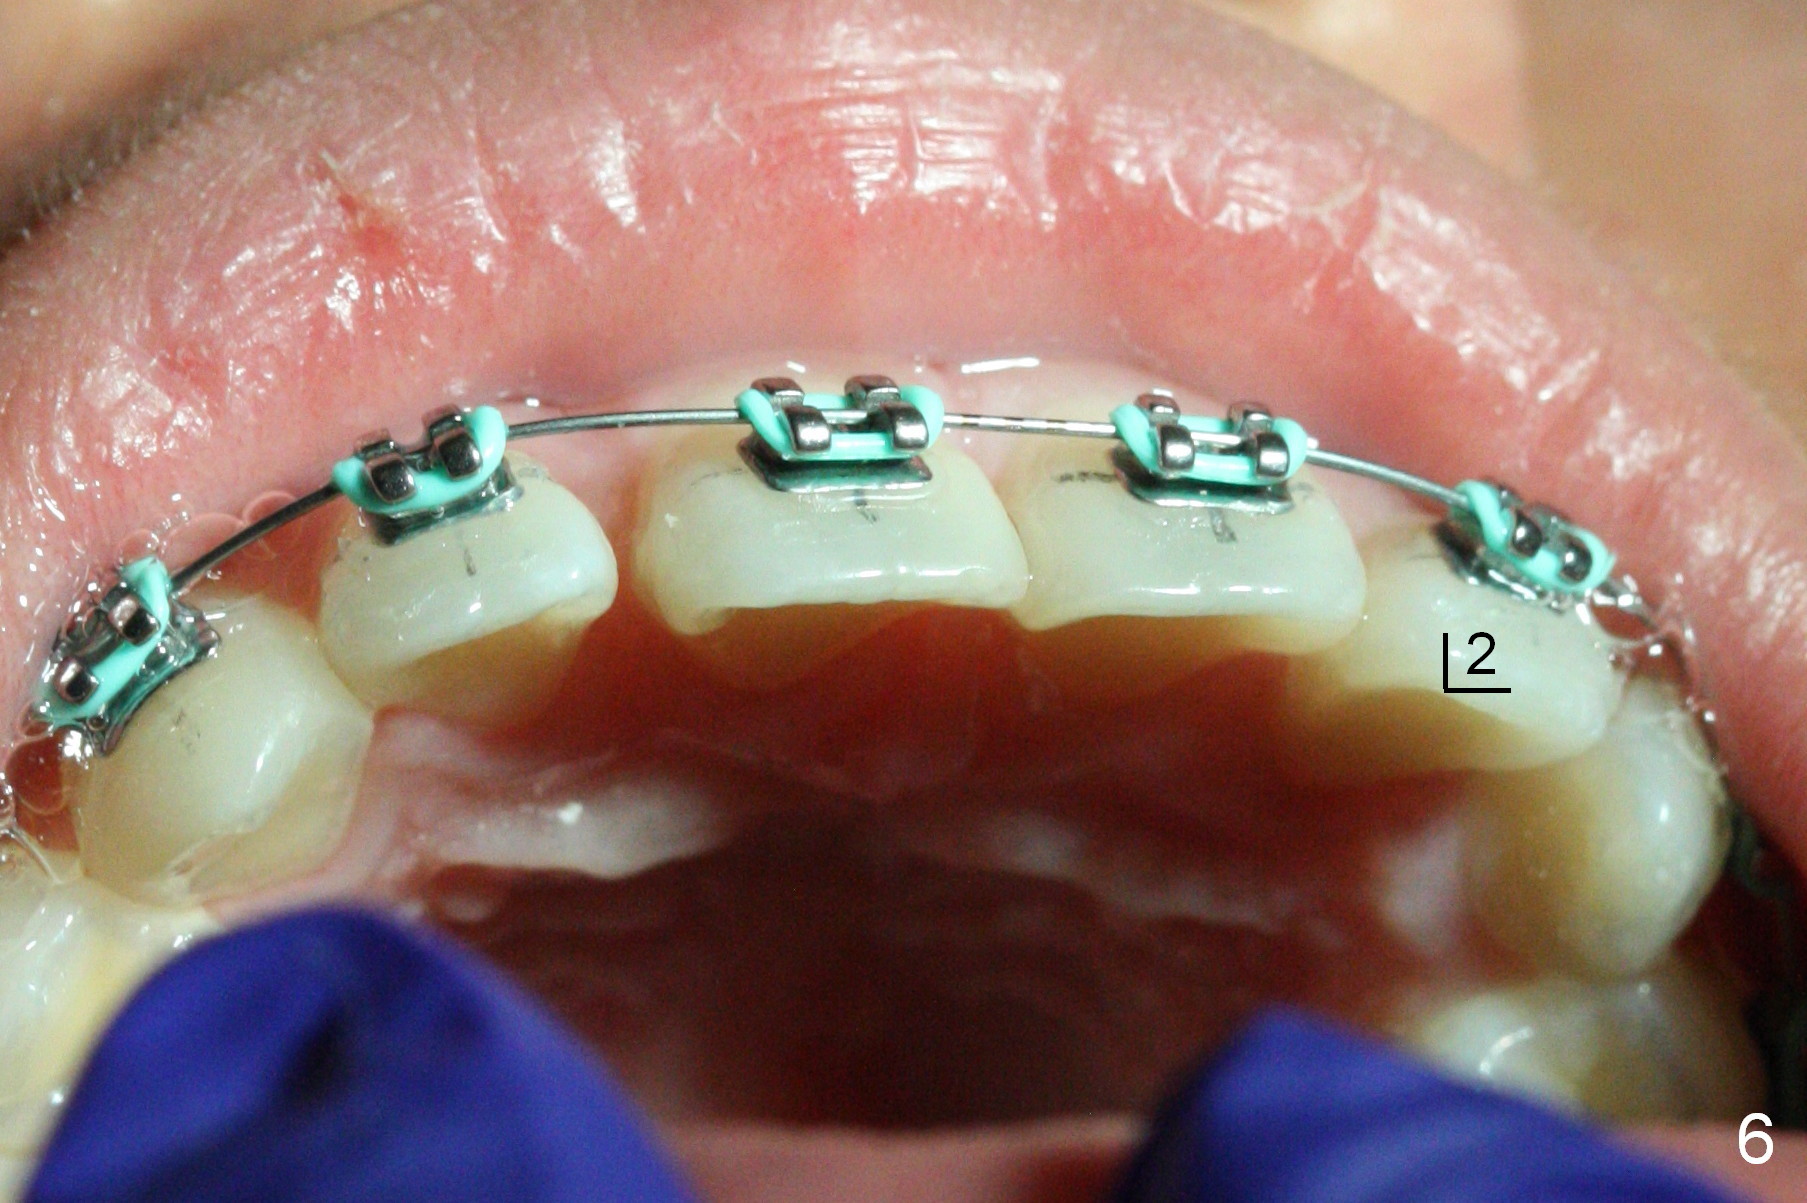

Ten days later UL2 returns to normal position (Fig.6). UR2 is slightly distally displaced; after removal of the rotation wedge at UR1, the same .014' niti wire is re-used (Fig.4). It is expected that UR2 should be able to return to normal position next visit. The wire engagement improves at LR1 (Fig.5). To facilitate LL1 wire engagement, power chain is placed between LL 1 and 3.